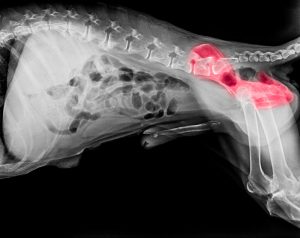

1. Hip Dysplasia

This is a genetic condition that affects the hip joints and can cause arthritis and lameness. To prevent hip dysplasia, it is important to choose a puppy from a reputable breeder who can provide health clearances for both parents.

3. Elbow Dysplasia

Like hip dysplasia, elbow dysplasia is a genetic condition that affects the elbow joints and can cause arthritis and lameness. To prevent elbow dysplasia, it is important to choose a puppy from a reputable breeder who can provide health clearances for both parents.